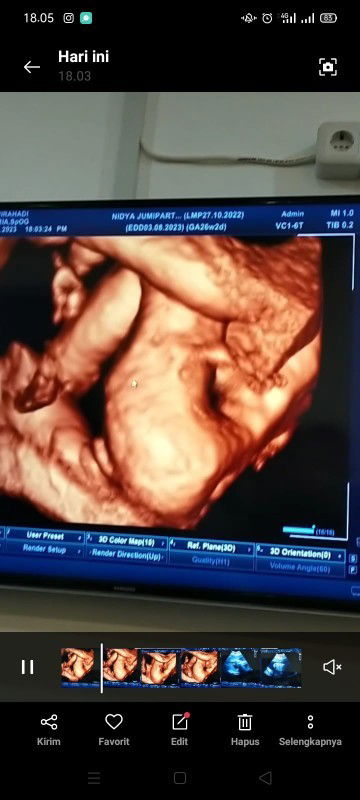

Assalamu'alaikum. Halo bun, saya minggu kemaren pas UK 26w USG 4D dan udah kelihatan banget Jenis Kelamin bayinya, saya mikir udah bisalah nyicil buat beli perlengkapan lahiran, tapi Ibu saya bilang nanti aja nyicilnya karena pengalaman Ibu dulu waktu hamil sama adek saya yg bungsu USG 3 kali cowok ternyata pas lahir cewek jadi mungkin takut mubazir perlengkapannya, karena saya rencana mau nyicil perlengkapan bayi yg custom gitu. Menurut bunda gimana yg udah pengalaman USG 4D apakah ada kemungkinan prediksi dokter keliru? Kalo feeling saya sih ini hasilnya jelas banget ya bun kalo JK nya cewek. Note: Kenapa saya mau nyicil sekarang karena saya selalu kontraksi palsu sampe diresepin dokternya obat penguat kandungan supaya tidak lahir prematur. Karena takutnya nanti tidak ada persiapan apa². #bantusharing #seriusnanya